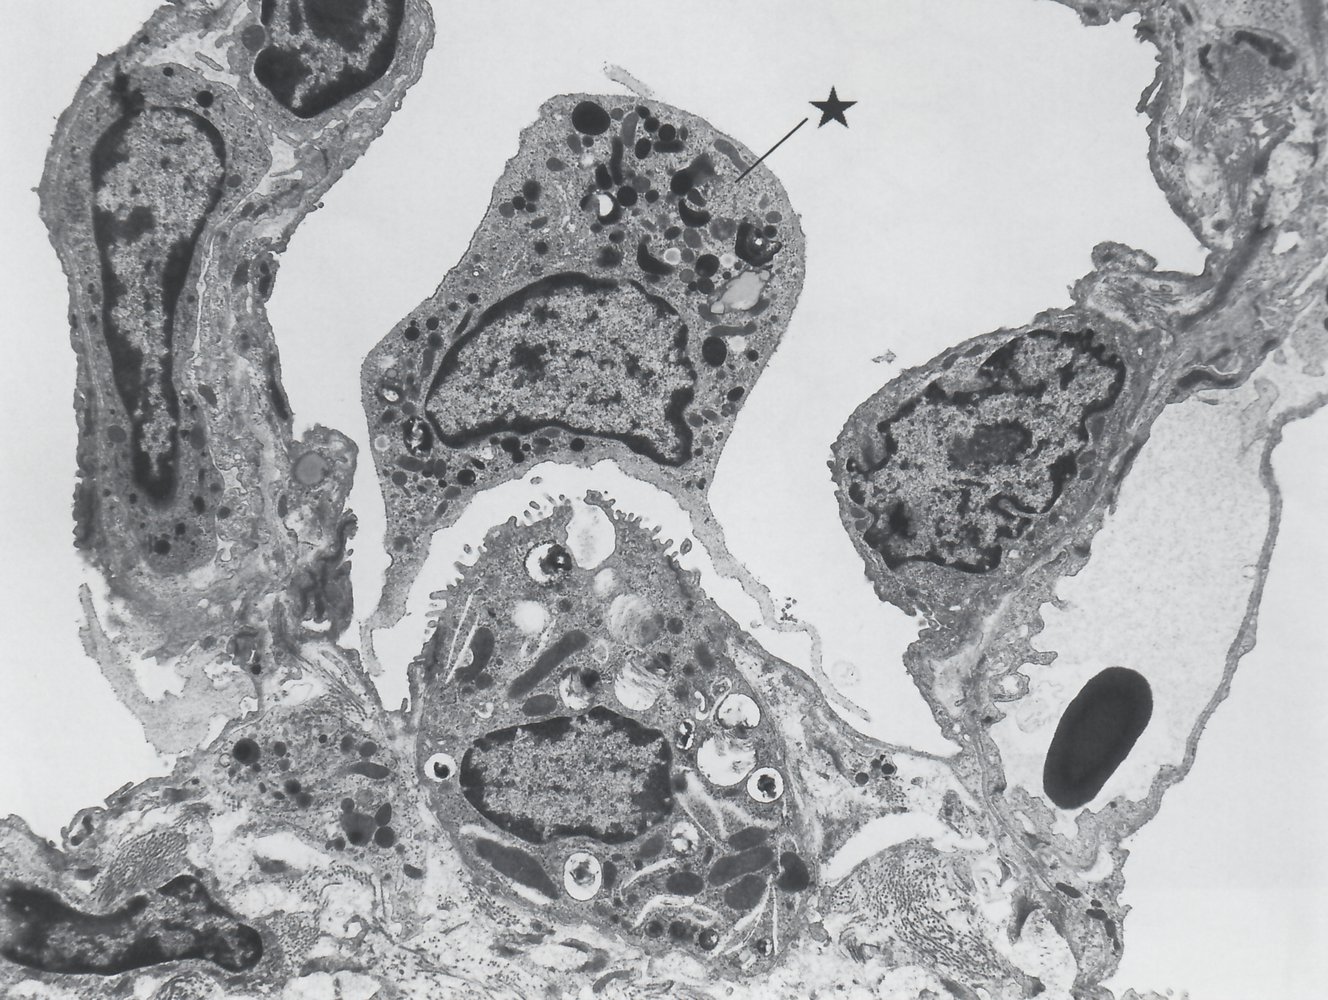

Pulmonary alveoli are separated from each other by the interalveolar septum with elastic fibers and capillaries. Interalveolar pores connect adjacent alveoli.

• Type I pneumocytes: thin squamous cells that line the alveoli that allow for transcellular gas exchange

• Comprise 95% of the total alveolar area

• Connected to each other by tight junctions

• Form the blood-air barrier, together with the endothelial cells of the capillaries and the basement membrane between the two cells.

• Type II pneumocytes: cuboidal alveolar cells

• Comprise 5% of the total alveolar area, but 60% of total number of cells

• Surfactant formation: Type II pneumocytes contain lamellar bodies, which secrete surfactant (surface-activating lipoprotein complex).

• Surfactant is mainly composed of the phospholipids dipalmitoylphosphatidylcholine (DPPC or lecithin) and phosphatidylglycerol.

• It reduces alveolar surface tension and thereby prevents the alveoli from collapsing.

• Lung regeneration and repair: Type II pneumocytes can proliferate to replace type I or type II pneumocytes following lung damage.

• Alveolar macrophages: phagocytose foreign materials and initiate the immune response by releasing cytokines